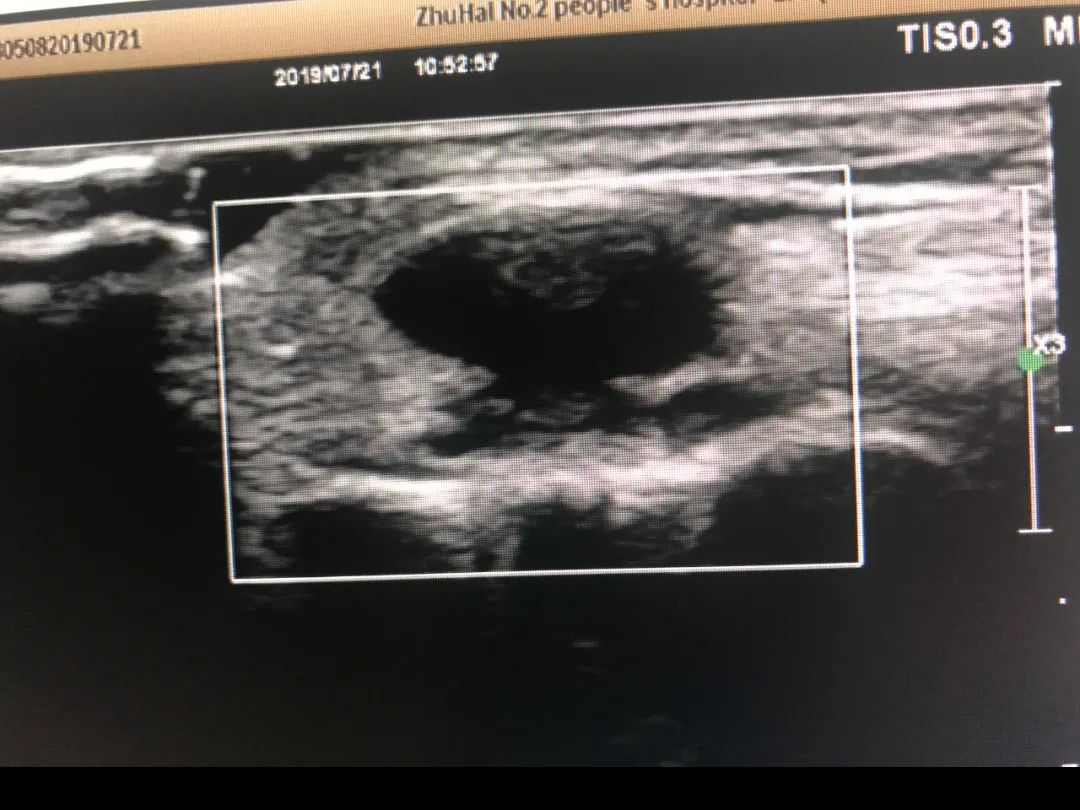

如果囊肿很容易触摸到,通过门诊透照即可方便地鉴别腱鞘囊肿与实体瘤:腱鞘囊肿透照阳性,而实体瘤透照呈阴性。 可采用超声检查帮助诊断腱鞘囊肿。大多数腱鞘囊肿边界清晰、厚壁和回声增强。实性外观的腱鞘囊肿虽然不常见,但可能酷似良性肿瘤。 在隐匿性腕部疼痛患者中,磁共振成像可区分大多数腱鞘囊肿与其他类型的肿块。

左图为手术前,右图为术后半年复发,比原来更大的囊肿